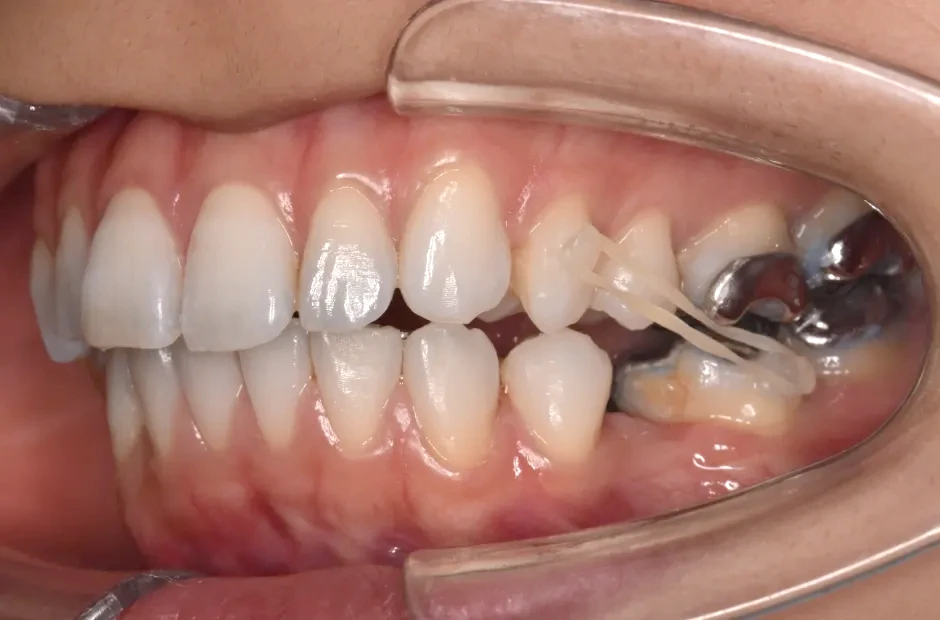

| 診断名・主訴 | 下顎前突、叢生 |

|---|---|

| 年齢・性別 | 23歳・女性 |

| 治療期間・回数 | 3年 |

| 治療に用いた主な装置 | 上顎5,5 下顎4,4 |

| 抜歯部位 | 舌側矯正 |

| 治療費 | 100万円(税抜) |

| リスク・副作用 | 装置による違和感・疼痛・歯肉退縮・歯根吸収・虫歯のリスクなど |

治療前

治療中

治療後